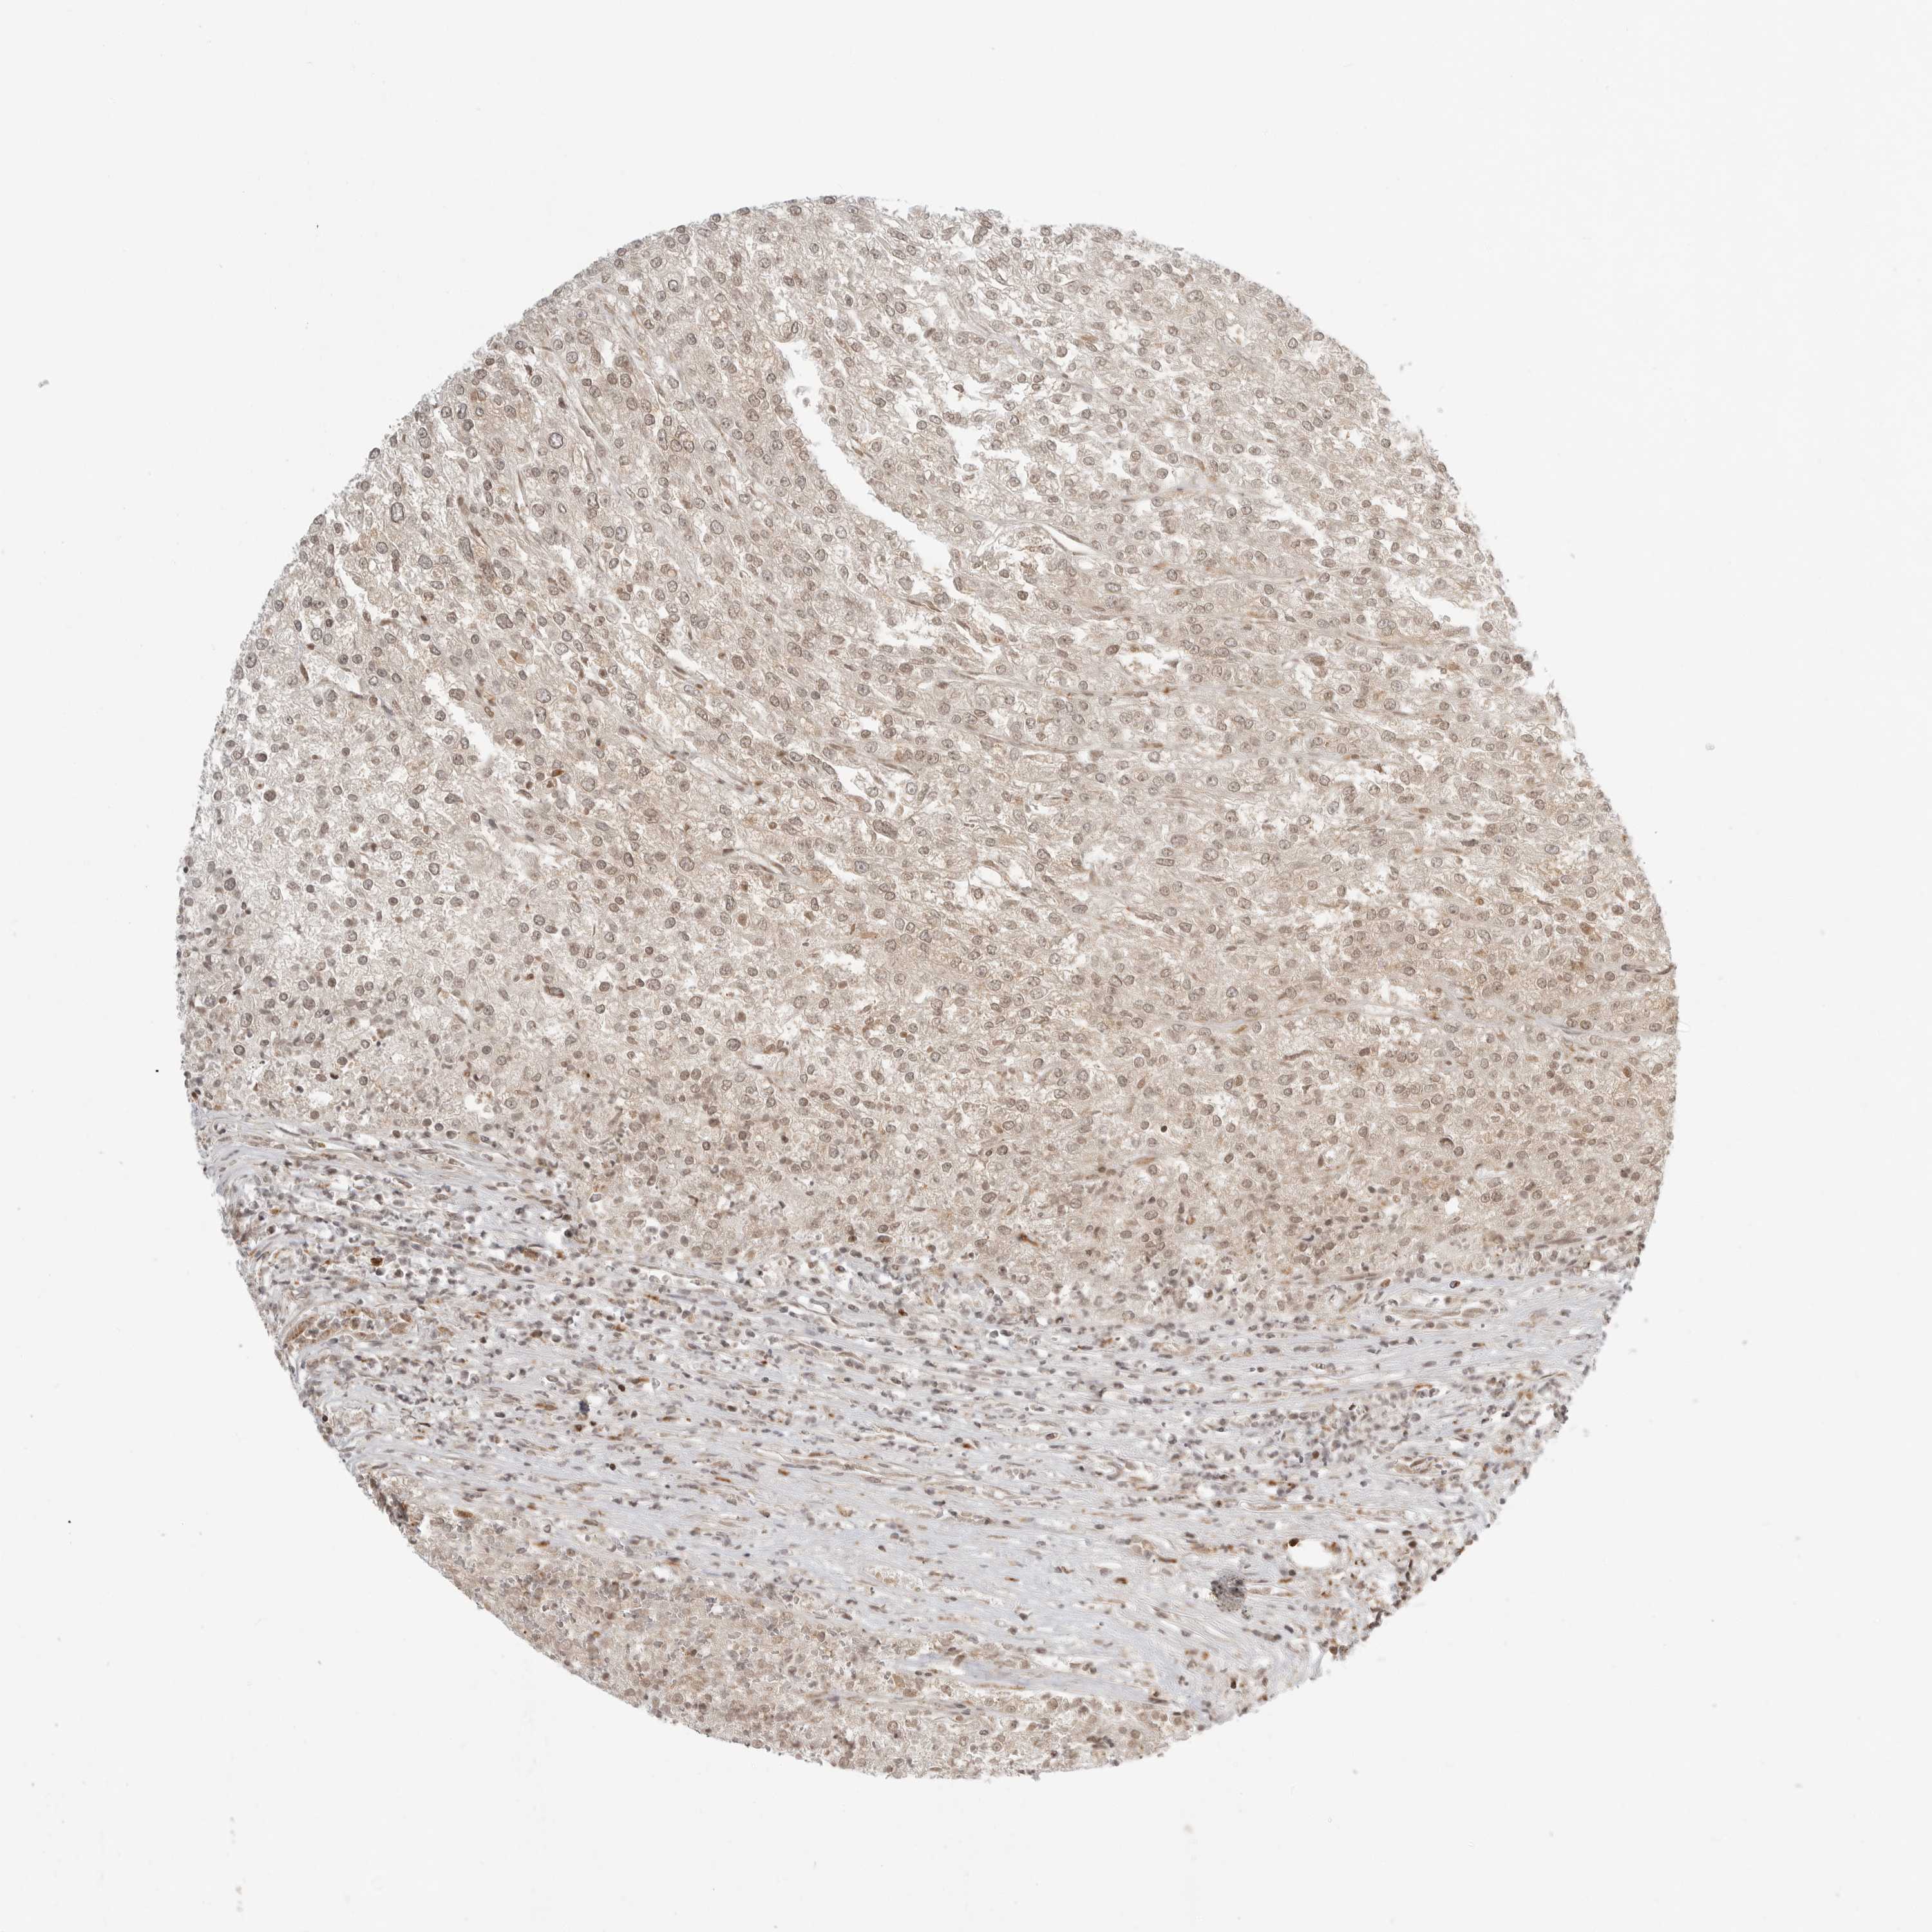

CANCER RENAL CANCER Show tissue menu

Renal cancer

Kidney chromophobe

KIDNEY CHROMOPHOBE (TCGA) - Interactive survival scatter ploti

The Survival Scatter plot shows the clinical status (i.e. dead or alive) for all individuals in the patient cohort, based on the same data that underlies the corresponding Kaplan-Meier plots. Patients that are alive at last time for follow-up are shown in blue and patients who have died during the study are shown in red.

The x-axis shows the expression levels (FPKM) of the investigated gene in the tumor tissue at the time of diagnosis. The y-axis shows the follow-up time after diagnosis (years). Both axes are complimented with kernel density curves demonstrating the data density over the axes. The top density plot shows the expression levels (FPKM) distribution among dead (red) and alive patients (blue). The right density plot shows the data density of the survived years of dead patients with high and low expression levels respectively, stratified using the cutoff indicated by the vertical dashed line through the Survival Scatter plot. This cutoff is automatically defined based on the FPKM cutoff that minimizes the p-score. The cutoff can be changed by dragging the vertical line or by entering a cutoff value in the square labeled "Current cut-off".

Under the Survival Scatter plot the p-score landscape (black curve; left axis) is shown together with dead median separation (red curve; right axis). Dead median separation is the difference in median mRNA expression between patients who have died with high and low expression, respectively. It is calculated as follows: median FPKM expression of dead patients with high expression - median FPKM expression of dead patients with low expression. This is intended to aid the user in visually exploring custom cutoffs and the associated p-scores and dead median separation.

Individual patient data is displayed and can be filtered by clicking on one or more of the category buttons on the top of the page. Categories describing expression level and patient information include: high, low, alive, dead, female, male and tumor stages. The scale of the x-axis can be toggled between linear and log-scale by clicking on the "x log" button. Mouse-over function shows TCGA ID, patient information and mRNA expression (FPKM) for each patient.

& Survival analysisi

Kaplan-Meier plots summarize results from analysis of correlation between mRNA expression level and patient survival. Patients were divided based on level of expression into one of the two groups "low" (under cut off) or "high" (over cut off). X-axis shows time for survival (years) and y-axis shows the probability of survival, where 1.0 corresponds to 100 percent.

IDUA is not prognostic in Kidney Chromophobe (TCGA)